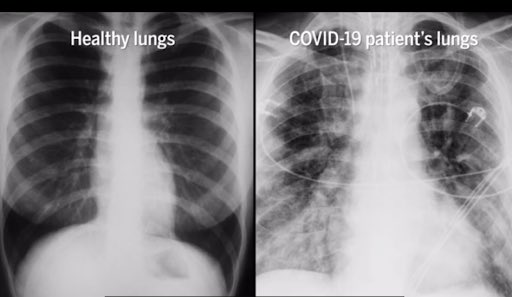

ASÍ SE VEN LOS PULMONES DE UNA PERSONA ENFERMA DE COVID-19

Sin importar los graves efectos que provoca el COVID-19, hay distintos grupos de personas que se niegan a utilizar cubrebocas,...